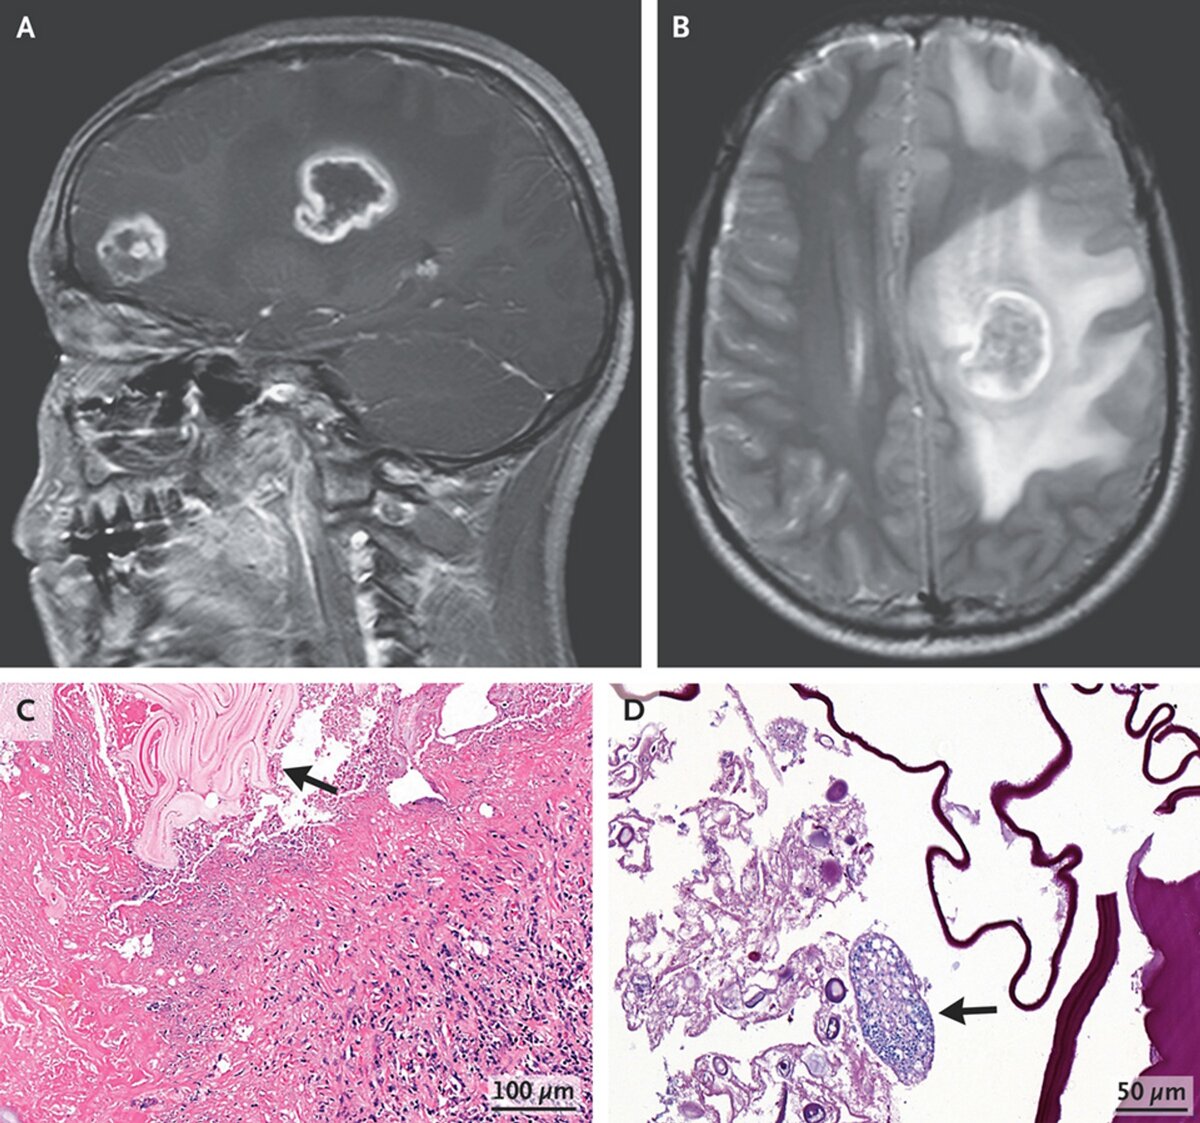

Сразу предупреждаем: эта история не для слабонервных. Китайские врачи описали редкий случай альвеококкоза (паразитарное заболевание), который был обнаружен у 17-летнего подростка. Как сообщает научно-популярное издание N+1 со ссылкой на отчет медиков, пациент поступил в отделение неотложной помощи с жалобами на головокружение, головную боль и мышечную слабость. В ходе хирургического вмешательства в мозге подростка обнаружили материал от ленточного червя — возбудителя альвеококкоза. Пациенту провели операцию и назначили длительный курс противопаразитарного препарата. Спустя два месяца подросток восстановился и симптомы прошли. Помимо пугающих подробностей, этот случай необычен еще и тем, что в 95% заражений паразит образует кисты в печени или легких, а на центральную нервную систему (мозг) приходится всего 2%. Кроме того, источником гельминтоза являются животные, в основном лисы. Однако пациент заверил врачей, что не контактировал с инфицированными животными.

Магнитно-резонансная томография головы подростка Фото: The New England Journal of Medicine